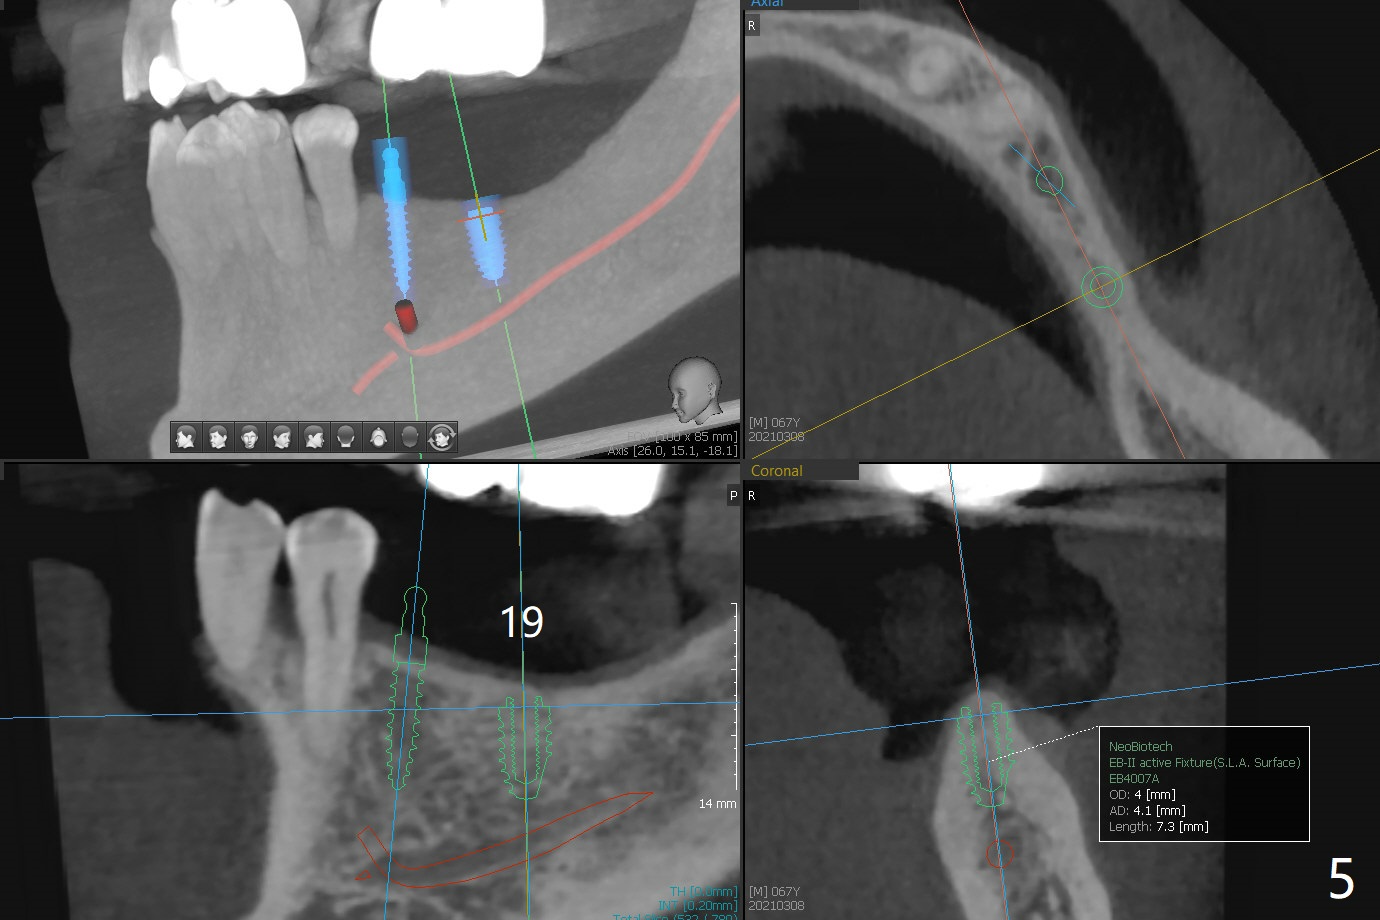

A 67-year-old man requests lower implants (19,20,25) to replace lower RPD with history of food impaction under the partial 5 months post cementation of the upper implants (Fig.1). Due to the atrophic mandible, 1-piece implants will be placed with guide (Fig.2-5) and free hand (Fig.6). Incision will be made at all of the sites for vision and bone graft.